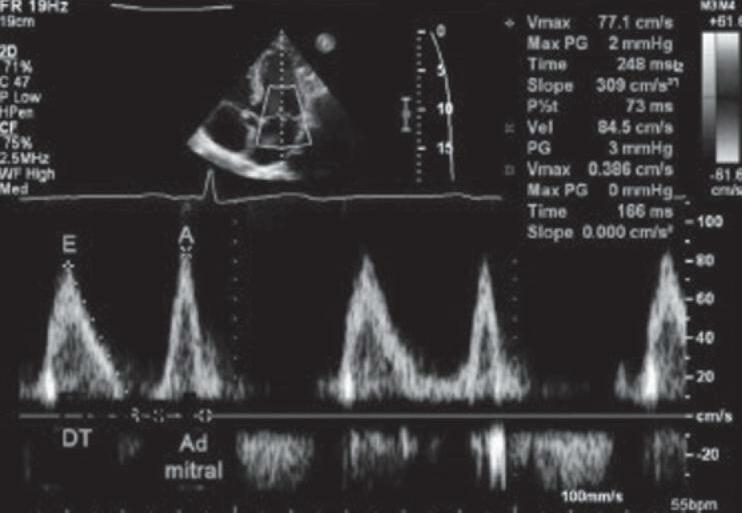

18 O Ecocardiograma no Manejo do Paciente Crítico, 193 Rodrigo Ferraz Salomão • Flávia Guimarães Brasil • Eduardo Boetner